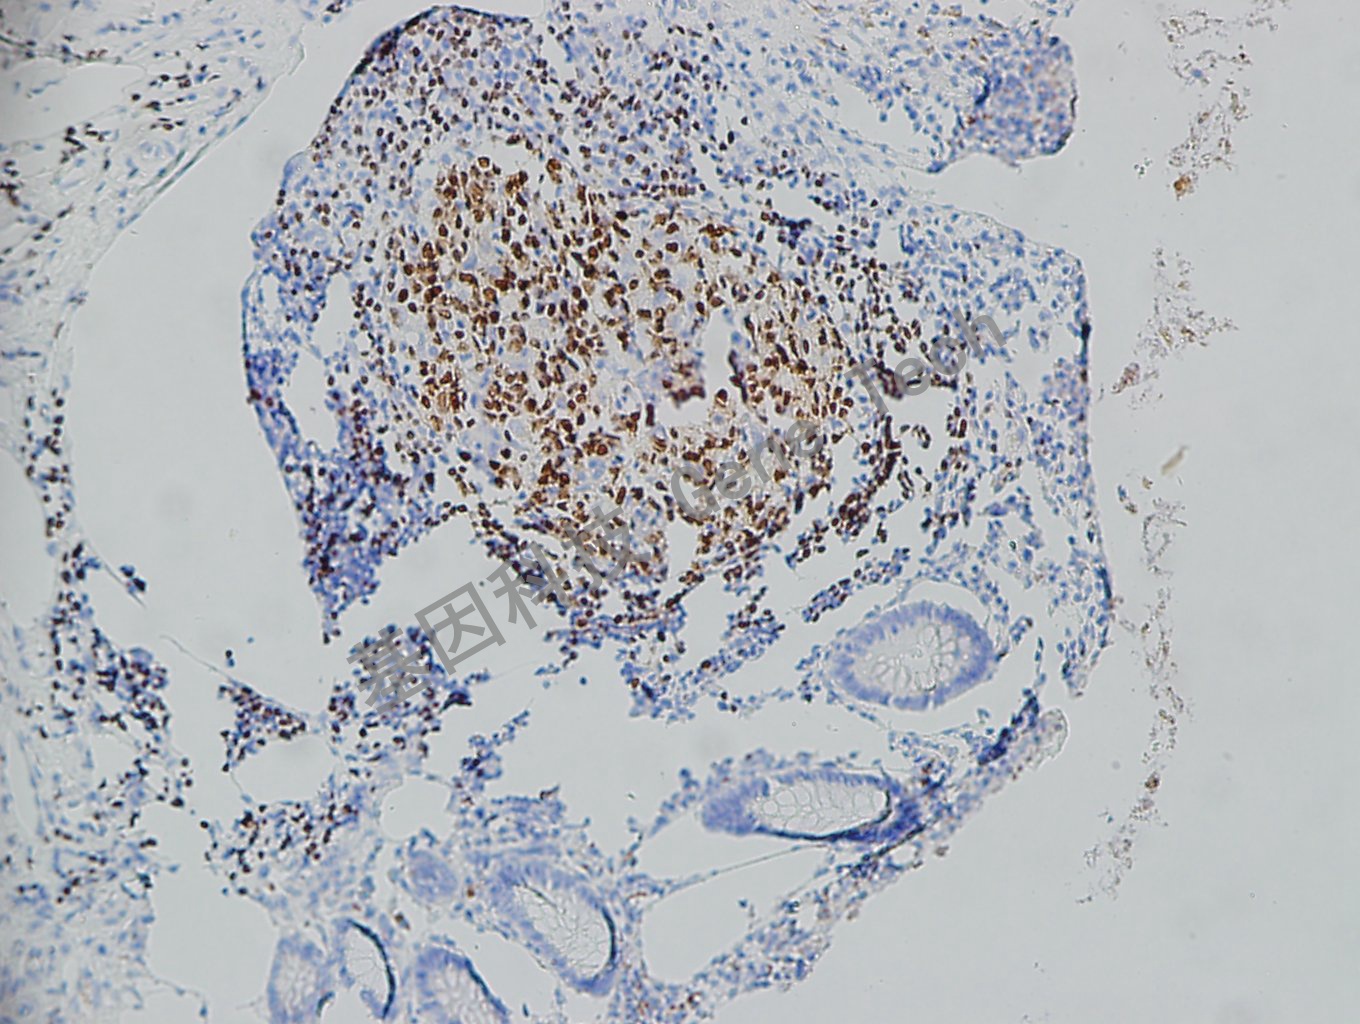

扁桃体石蜡切片,用 PAX-5(GT2096)染色,B 细胞胞核阳性,DAB 显色。

阑尾石蜡切片,用 PAX-5(GT2096)染色,细胞核阳性,DAB 显色。